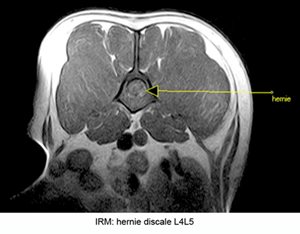

L'imagerie par résonance magnétique nucléaire (IRM).

Si quelques centres vétérinaires sont équipés en appareils dits de "bas champs", le développement de l'IRM en médecine vétérinaire en France reste encore à ses balbutiements. Lla carence en appareils performants dits de "haut champs" est une limite importante quant à la qualité des examens permise par la plupart des appareils actuellement accessibles.

Sur le rachis, sauf pour le diagnostic des kyste arachnoïdiens, du syndrome de Harnold Chiari, ou de certaines lésions intra-médullaires, les machines de bas champs sont moins performantes que les scanners multicoupes (dits multibarettes) désormais facilement disponibles en médecine vétérinaire.

La durée de l'examen par IRM, la très faible répartition géographique des appareils, leur manque de puissance et le coût très supérieur de l'examen par rapport à un scanner, font de l'IRM un examen de deuxième intention en terme d'exploration du rachis en médecine vétérinaire.

Il est par ailleurs important de noter qu'en médecine humaine, où les machines de haut champs très performantes sont pourtant facilement accessible, c'est les scanner qui demeure l'examen de première intention sur la colonne vertébrale.